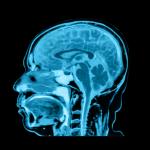

Психолозите наричат феномена на това да се чувствате по-млади от реалната си възраст субективна възраст. За целите на своето изследване те са набрали 68 здрави възрастни участници, които са били на възраст между 59 и 84 години, и са ги интервюирали за това, на каква реална възраст са били и на каква са се усещали. Едновременно с това на участниците са им били правени мозъчни сканирания, които е трябвало да определят обема сиво вещество в някои специфични области на мозъка.